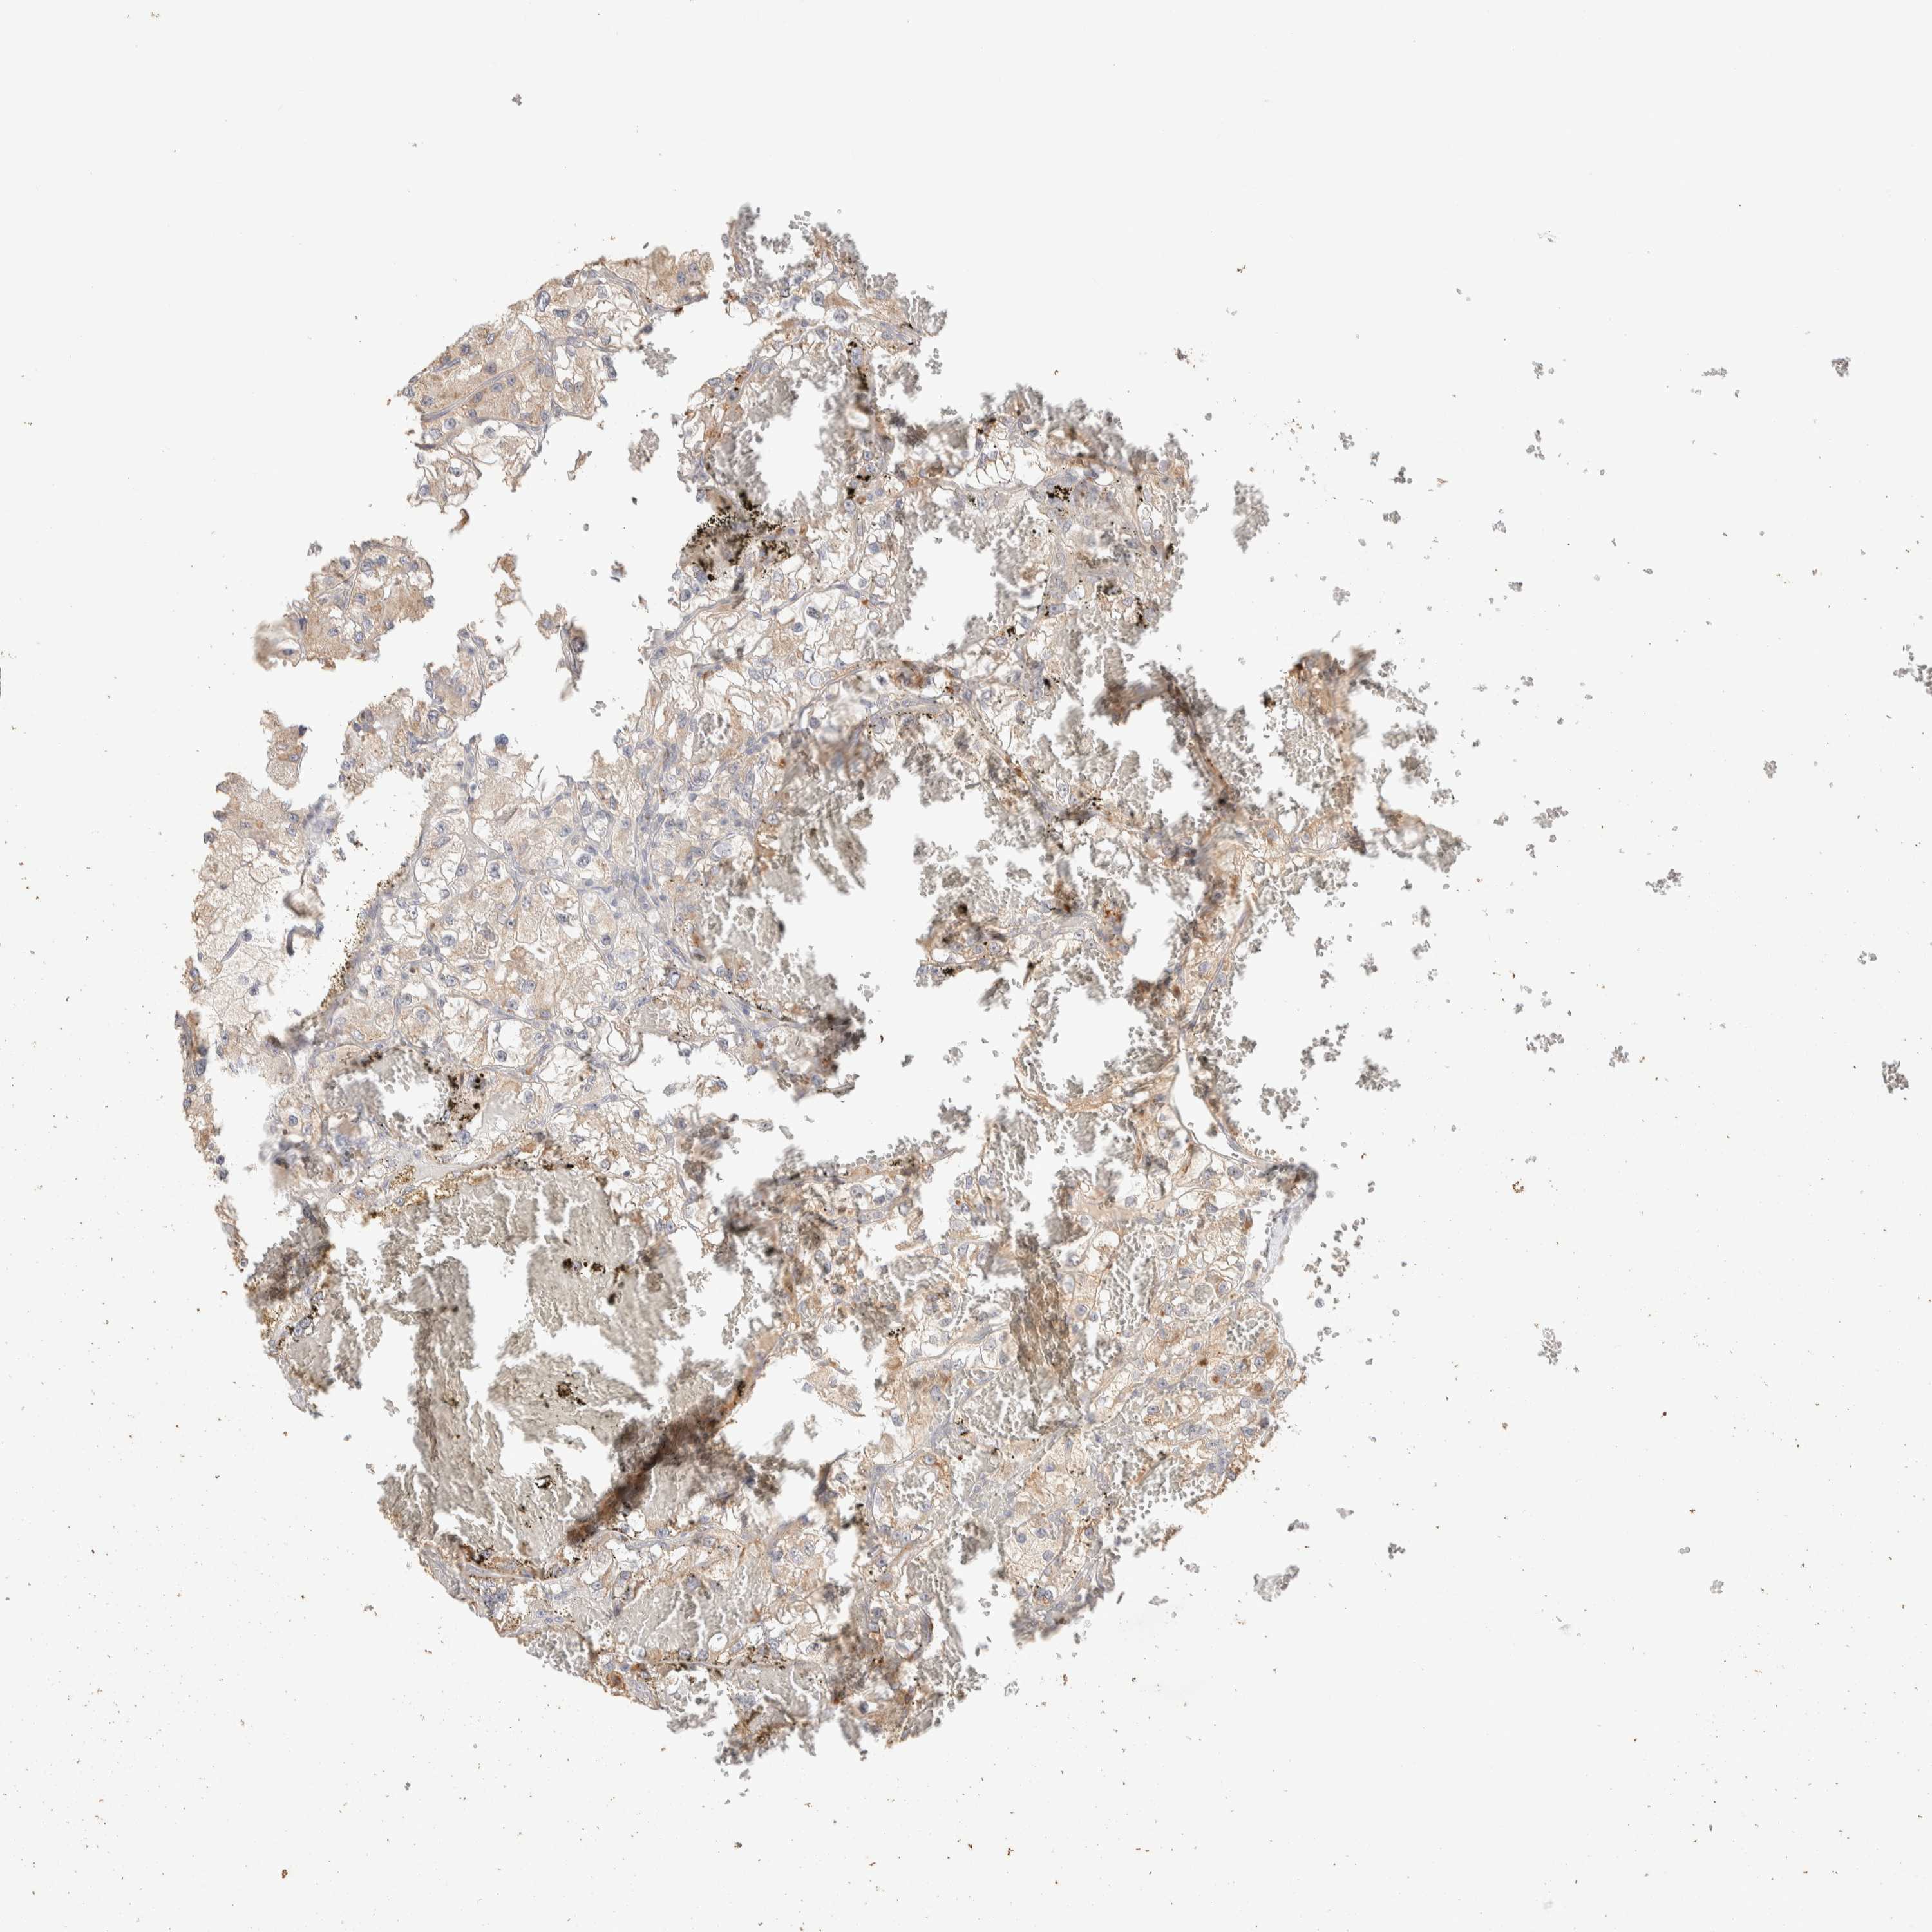

KIDNEY RENAL CLEAR CELL CARCINOMA (VALIDATION) - Interactive survival scatter ploti

The Survival Scatter plot shows the clinical status (i.e. dead or alive) for all individuals in the patient cohort, based on the same data that underlies the corresponding Kaplan-Meier plots. Patients that are alive at last time for follow-up are shown in blue and patients who have died during the study are shown in red.

The x-axis shows the expression levels (FPKM) of the investigated gene in the tumor tissue at the time of diagnosis. The y-axis shows the follow-up time after diagnosis (years). Both axes are complimented with kernel density curves demonstrating the data density over the axes. The top density plot shows the expression levels (FPKM) distribution among dead (red) and alive patients (blue). The right density plot shows the data density of the survived years of dead patients with high and low expression levels respectively, stratified using the cutoff indicated by the vertical dashed line through the Survival Scatter plot. This cutoff is automatically defined based on the FPKM cutoff that minimizes the p-score. The cutoff can be changed by dragging the vertical line or by entering a cutoff value in the square labeled "Current cut-off".

Under the Survival Scatter plot the p-score landscape (black curve; left axis) is shown together with dead median separation (red curve; right axis). Dead median separation is the difference in median mRNA expression between patients who have died with high and low expression, respectively. It is calculated as follows: median FPKM expression of dead patients with high expression - median FPKM expression of dead patients with low expression. This is intended to aid the user in visually exploring custom cutoffs and the associated p-scores and dead median separation.

Individual patient data is displayed and can be filtered by clicking on one or more of the category buttons on the top of the page. Categories describing expression level and patient information include: high, low, alive, dead, female, male and tumor stages. The scale of the x-axis can be toggled between linear and log-scale by clicking on the "x log" button. Mouse-over function shows TCGA ID, patient information and mRNA expression (FPKM) for each patient.

& Survival analysisi

Kaplan-Meier plots summarize results from analysis of correlation between mRNA expression level and patient survival. Patients were divided based on level of expression into one of the two groups "low" (under cut off) or "high" (over cut off). X-axis shows time for survival (years) and y-axis shows the probability of survival, where 1.0 corresponds to 100 percent.

ITPA is potential prognostic, high expression is unfavorable in Kidney Renal Clear Cell Carcinoma (validation)

Best expression cut offi

Based on the FPKM value of each gene, patients were classified into two groups and association between prognosis (survival) and gene expression (FPKM) was examined. The best expression cut-off refers the FPKM value that yields maximal difference with regard to survival between the two groups at the lowest log-rank P-value. Best expression cut-off was selected based on survival analysis .

When clicking on this number, the vertical dashed line indicating cut-off, the interactive survival plot, and the Kaplan-Meier curve will be adjusted to show results based on the best expression cut-off.

: 53.69

P scorei

Log-rank P value for Kaplan-Meier plot showing results from analysis of correlation between mRNA expression level and patient survival.

N/A

5-year survival highi

5-year survival for patients with higher expression than the expression cutoff.

For melanoma and glioma, 3-year survival is shown.

5-year survival lowi

5-year survival for patients with lower expression than the expression cutoff.

TCGA RNA samplesi

RNA-seq data is reported as average FPKM (number Fragments Per Kilobase of exon per Million reads), generated by the The Cancer Genome Atlas (TCGA) .

Normal distribution across the dataset is visualized with box plots, shown as median and 25th and 75th percentiles. Points are displayed as outliers if they are above or below 1.5 times the interquartile range. FPKM values of the individual samples are presented next to the box plot.

Average pTPM 47.8

Number of samples 100